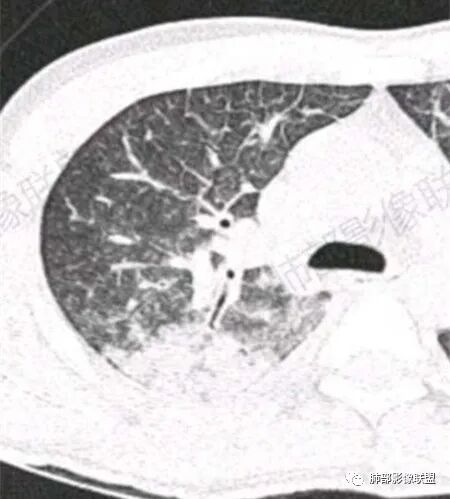

青年男性患者,气促7小时入院,白细胞及中性粒明显增高,PCT增高,CRP不高,心率快,呼吸急促,意识模糊,低氧血症,I型呼吸衰竭,PH偏低,失代偿性酸中毒,BNP偏高,胸部CT:双肺弥漫性多发斑片状实变密度影,双上肺明显,间质改变为主,综合:年轻男性,急性起病,迅速恶化,考虑中毒可能,鉴别:PCP,过敏,

双肺上叶,下叶背段多发斑片状实变影,以胸膜下分布为主,部分重力作用,以背侧为主,部分小叶间质增厚,部分周围伴有散在磨玻璃影,边界欠清,临床急性病程,血象增及PCT明显增高,意识模糊,考虑:吸入性肺炎?鉴别:AHP?CEP?PCP

37岁男性 气促 两肺对称分布磨玻璃及小叶间隔增厚,两肺上叶后段及下叶背段为著,有重力分布,下部密度较高,请结合病史排查肺水肿,理化性肺泡损伤

双肺叶透亮度对称性减低,呈磨砂状,小叶间隔规则增厚,上叶为甚,左右肺叶中轴间质增厚(示淋巴回流障碍),双肺叶弥散磨GGO征,以肺腺泡分布,双肺上,下叶融合片状,有重力分布特点,心脏大,肺动脉干增粗,首选心源性肺水肿,但无胸腔积液。与急性肺损伤和ARDS鉴别

影像:两肺上叶小叶间隔增厚,斑片,腺泡结节,重力分布,下肺不累及

影像学提示肺水肿与肺泡腔液性渗出(小叶间隔增厚+实变+重力趋势),上叶显著。

双肺弥漫性病变以上肺,向心性,背部分布为主,肺动脉干无增粗,急性起病,典型的吸入性肺炎。

青年男性,气促7小时入院,意识模糊,白细胞及中性粒明显增高,PCT增高,CRP不高,心率快,体温正常,血压正常。胸部CT:双肺上叶小叶间隔光滑增厚,中轴间质增厚,弥漫性磨玻璃、多发斑片影,以上肺、背侧分布为主。影像表现考虑为肺水肿。病因:病史不支持肾功能衰竭、心源性、高原性肺水肿,无发热,似乎也不支持细菌、病毒、真菌等感染引起。吸入毒物?吸入水?

对称性小叶间隔增厚

高密度影重力趋势

病灶的分布以上肺为主

确实要考虑吸入,倾向于吸入的是气体类的可能,因为朝上走